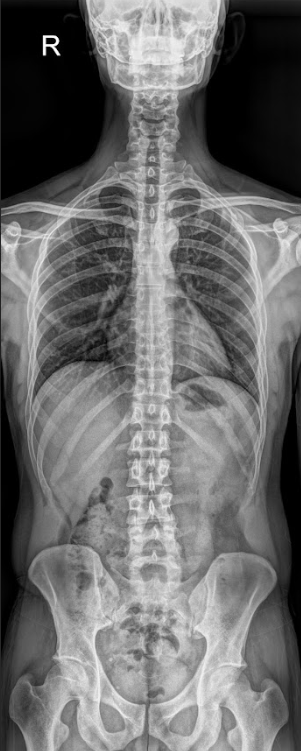

구조적 원인 분석 (Whole Spine X-ray)

협력 영상의학과에서 촬영한 엑스레이를 통해 경추부터 골반까지 척추 전체의 배열 상태를 정밀하게 분석합니다.

틀어진 배열은 자율신경 통로의 압박 가능성을 시각적으로 보여주는 강력한 단서가 됩니다.

10회 단위로 재촬영하여

구조적 변화가 어떤 흐름으로

연결되는지 직접 확인합니다.